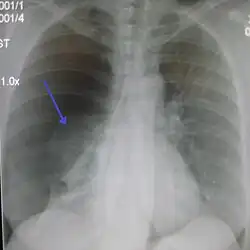

Chest X-ray

A plain chest radiograph, ideally with the X-ray beams being projected from the back (posteroanterior, or "PA"), and during maximal inspiration (holding one's breath), is the most appropriate first investigation.[35] It is not believed that routinely taking images during expiration would confer any benefit.[36] Still, they may be useful in the detection of a pneumothorax when clinical suspicion is high but yet an inspiratory radiograph appears normal.[37] Also, if the PA X-ray does not show a pneumothorax but there is a strong suspicion of one, lateral X-rays (with beams projecting from the side) may be performed, but this is not routine practice.[18][22]

Anteroposterior inspired X-ray, showing subtle left-sided pneumothorax caused by port insertion -

Chest X-ray showing a pneumothorax on the right (left in the image), where the absence of lung markings indicates that there is free air inside the chest -

It is not unusual for the mediastinum (the structure between the lungs that contains the heart, great blood vessels, and large airways) to be shifted away from the affected lung due to the pressure differences. This is not equivalent to a tension pneumothorax, which is determined mainly by the constellation of symptoms, hypoxia, and shock.[16]

The size of the pneumothorax (i.e. the volume of air in the pleural space) can be determined with a reasonable degree of accuracy by measuring the distance between the chest wall and the lung. This is relevant to treatment, as smaller pneumothoraces may be managed differently. An air rim of 2 cm means that the pneumothorax occupies about 50% of the hemithorax.[18] British professional guidelines have traditionally stated that the measurement should be performed at the level of the hilum (where blood vessels and airways enter the lung) with 2 cm as the cutoff,[18] while American guidelines state that the measurement should be done at the apex (top) of the lung with 3 cm differentiating between a "small" and a "large" pneumothorax.[38] The latter method may overestimate the size of a pneumothorax if it is located mainly at the apex, which is a common occurrence.[18] The various methods correlate poorly but are the best easily available ways of estimating pneumothorax size.[18][22] CT scanning (see below) can provide a more accurate determination of the size of the pneumothorax, but its routine use in this setting is not recommended.[38]

Not all pneumothoraces are uniform; some only form a pocket of air in a particular place in the chest.[18] Small amounts of fluid may be noted on the chest X-ray (hydropneumothorax); this may be blood (hemopneumothorax).[16] In some cases, the only significant abnormality may be the "deep sulcus sign", in which the normally small space between the chest wall and the diaphragm appears enlarged due to the abnormal presence of fluid.[19]